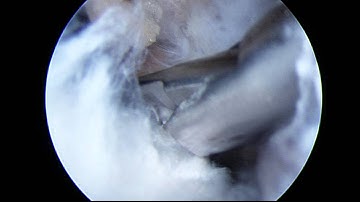

Suprascapular Nerve Decompression Case - Part 1